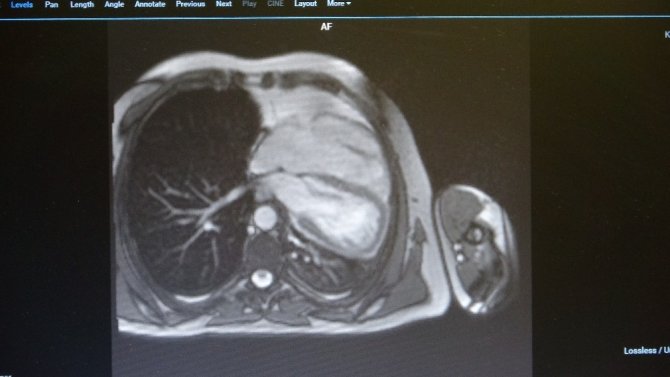

Isparta'da akciğer rahatsızlığı dolayısıyla gittiği hastanede, kalp rahatsızlığı kontrolü için Kardiyoloji'ye sevk edilen 45 yaşındaki erkek hastanın kalp zarının doğuştan bulunmadığı ortaya çıktı. İlk etapta kalbi delik olduğundan şüphe edilen hastanın gerekli kontrolleri yapıldığında, doğuştan kalp zarının bulunmadığı ve kalp aksının normal insanlara göre sola eğik şekilde olduğu tespit edildi.

Dünyada şu ana kadar bildirilen 400, Türkiye'de ise bildirilen yalnızca 4 vak'anın bulunduğunu ifade ederek İhlas Haber Ajansı (İHA) Muhabiri'ne açıklamalarda bulunan Isparta Şehir Hastanesi Kardiyoloji Uzmanı Uz.Dr.Mehtap Yeni, "Hastamız, kalpte delik şüphesiyle bana yönlendirilmişti, sonrasında yaptığımız tetkiklerde kalp zarının olmadığını fark ettik. Çok nadir görülen bir hastalık. Bu durum hastanemizde çekilen Kardiyak MR ile daha net bir şekilde koyulabiliyor. Şüphe etmemiz Eco vasıtasıyla oldu. Eco'da hastanın kalbinin, sol tarafa doğru çok eğik olması bize tanıda şüphe ettirdi. Daha sonrasında Kardiyak MR, kalbin tomografisi sonrasında hastanın tanısını koymuş olduk" dedi.

Uz.Dr. Yeni hastanın genel durumu hakkında ise şu değerlendirmelerde bulundu; "Hastanın çok ciddi şikayetleri yok. Ciddi şikayetleri olmadığı için MR bulgularına bakarak şunu söyleyebilirim; hastanın şu anda ciddi bir endikasyonu yok. En azından şu ana kadar böyle bir durum yok. Hastamız 45 yaşında ve şu ana kadar ciddi bir şikayeti olmamış. Bu hastalıkta MR bulgularına bakarak, biz hastanın riskini değerlendiriyoruz. Kalbin eğer, o zarın olmadığı yerden fıtıklaşması söz konusuysa, kalbe giren - çıkan damarlarda bası söz konusuysa, o zaman ciddi cerrahi endikasyon doğmakta. Bu hastada şimdiye kadar biz böyle bir şey tespit etmedik".